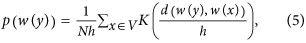

Intravascular filling defects (IVFD) are a feature of MR that can be observed in fluorescein angiogram (FA) images. IVFD may represent sequestration of parasitised erythrocytes in the microvasculature5. Sequestration is the pathological hallmark of cerebral malaria6,7, but as yet, it has only been possible to quantify it histopathologically at post mortem. IVFD can be seen in large and small venules, arterioles and capillaries, but appear to be most prominent in venules. As shown in Fig. 1, the appearance ranges from mottling and slight irregularities of the vessel wall, to more obvious lesions that look as if small bites have been taken from the vessel4,8. Cerebral and retinal sequestration is always seen in fatal cases of CM with MR2,9 and the histopathological appearance of sequestration is similar to IVFD2,10. Moreover, IVFD often resolve the day after treatment with anti-malarial drugs is started (personal observation). This is consistent with resolution of sequestration and clinical recovery. It is plausible that IVFD represent this fundamental pathological process and this lesion merits further investigation.

Two example fluorescein angiography images illustrating the appearances of IVFDs.

Vessels with IVFD are shown by single arrows. Vessels without IVFD, in the same image, are shown by double arrows.(a) Example 1: Intensity of mature parasitized red blood cells in vessels with IVFD is significantly different from normal vessels. (b) Example 2: Edges of vessels with IVFDs become unsmooth, the diameter is changed dramatically when compared to normal vessels. The images on the right are the zoom-in view of the regions enclosed by the green box within the original image on the left respectively.

In the case of IVFD, there is a contrast between the normally smooth vessel wall and individual discrete lesions that appear to protrude into the vessel lumen (Fig. 1(a)). These lesions may be defined as salient regions. Similarly, in the vessels affected by IVFD, some sections of the diameters or curvatures of vessel walls may be significantly different from neighbouring vessels or even other segments of the same vessel (Fig. 1(b)), such vessel edges may also be determined as salient features. These observations prompted us to use vessel intensity and shape saliency maps and combine them to generate a combined saliency map.